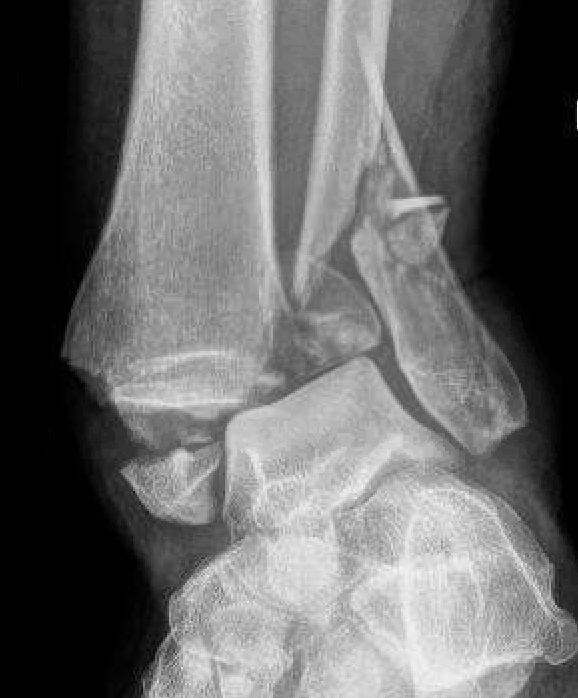

Bimalleolar fractures

Medial malleolus + Weber B lateral malleolus

Medial malleolus + Weber C lateral malleolus